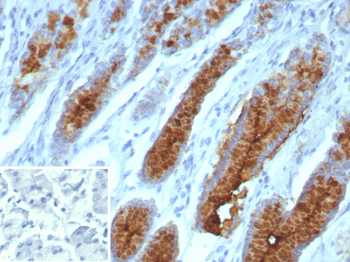

Formalin-fixed, paraffin-embedded human stomach stained with MUC5AC Recombinant Rabbit Monoclonal (MUC5AC/7066R). Inset: PBS instead of primary antibody; secondary only negative control.